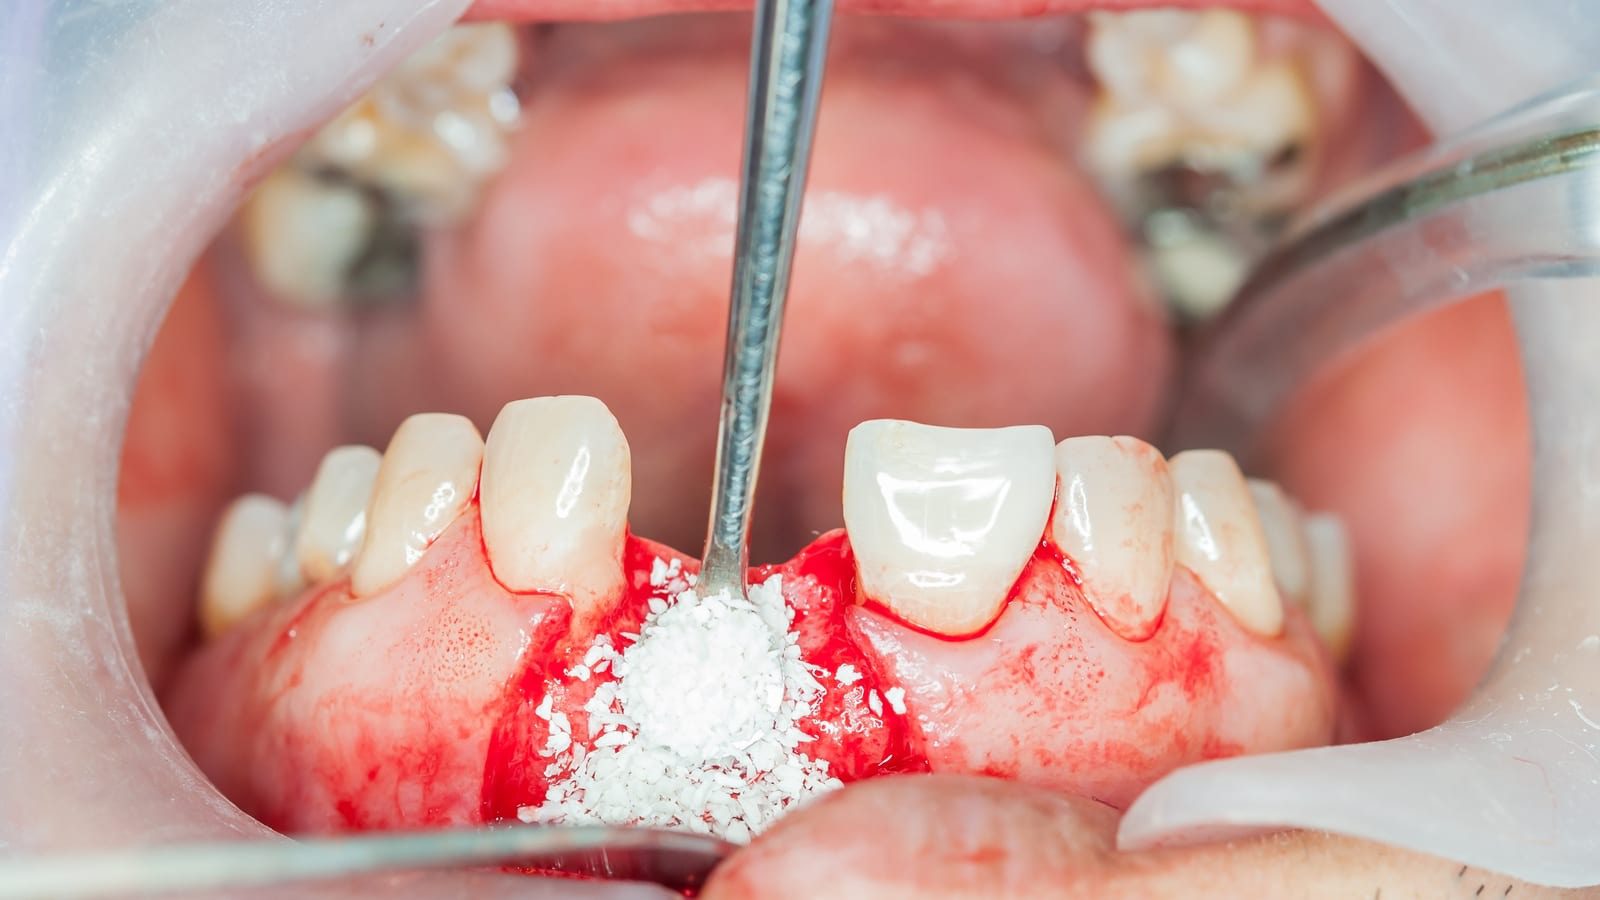

پودر استخوانی معمولا از بافت استخوان خرد شده به دست میآید و به صورت دانههای ریز در نواحی دچار کمبود استخوان قرار میگیرد و به عنوان یک ماده بیولوژیک با تحریک فرآیندهای ترمیمی به بازسازی استخوان کمک میکند. در واقع این ماده برای ترمیم ضایعات کوچک استخوانی مورد استفاده قرار میگیرد. در مقابل گرافت استخوانی به طور کلی به تودههای استخوانی با ساختار سهبعدی اطلاق میشود که میتواند از انواع مختلفی مانند بلوکهای استخوانی، گرافتهای ترکیبی با مواد مصنوعی ساخته شود. این گرافتها علاوه بر داشتن ویژگیهای پودر استخوانی، معمولا دارای ساختارهای بزرگتر و مقاومتری هستند که میتوانند در نواحی با کمبود شدید استخوان یا در فرآیندهای پیچیدهتر مانند لیفت سینوس و بازسازی استخوانهای فک استفاده شوند. در نهایت انتخاب میان پودر استخوانی و گرافت استخوانی بستگی به شرایط بالینی خاص، شدت کمبود استخوان و نیازهای ترمیمی هر بیمار دارد.

گفتنی است که پودر استخوانی باید تخلخل مناسب داشته باشد تا فضای کافی برای رشد سلولهای استخوانی فراهم شده و همچنین نفوذ مایعات در داخل آن برای رشد سلول اتفاق بیافتد.

ترکیب مناسبی از میکروپروز و ماکروپروز باعث میشود که پودر استخوانی هم سطح تماس زیاد برای واکنشهای شیمیایی داشته باشد و هم فضای کافی برای بازسازی و رشد استخوان واقعی ایجاد کند.

هدایت استخواان سازی (Osteoconduction): در این حالت پودر نقش داربست (Scaffold) را ایفا میکند یعنی استخوان نمیسازد ولی ساختار سه بعدی ایجاد میکند که سلولهای بدن بتوانند روی آن رشد کنند ودرون حفرات آن استخوان بسازند. این ویژگی در بسیاری از گرافتها به ویژه زنوگرافتها و مواد سینتتیک دیده میشود.

در مجموع میتوان گفت پودر استخوانی به عنوان یکی از پرکاربردترین مواد جایگزین در حوزه دندانپزشکی و جراحیهای فک و صورت، نقشی کلیدی در بازسازی و ترمیم بافتهای استخوانی ایفا میکند. این ماده نه تنها به عنوان یک داربست زیستی عمل کرده و محیط مناسبی را برای رشد و تکثیر سلولهای استخوان ساز فراهم میآورد بلکه در بسیاری از موارد طی فرآیند بازسازی تدریجی با استخوان طبیعی بدن جایگزین میشود. بدین ترتیب پس از گذشت چند ماه، ناحیه درمان شده دارای تراکم و استحکام کافی خواهد بود و شرایط ایدهآل برای قراردادن ایمپلنتهای دندانی ایجاد میگردد. استفاده از پودر استخوانی علاوه بر افزایش موفقیت درمانهای ایمپلنتولوژی، به بهبود زیبایی، عملکرد و پایداری طولانی مدت پروتزهای دندانی کمک شایانی میکند. بنابراین میتوان نتیجه گرفت که به کارگیری این ماده دردندانپزشکی مدرن، رویکردی علمی و کارآمد برای ارتقای کیفیت درمانهای بازسازی و جایگزینی دندان به شمار میرود.